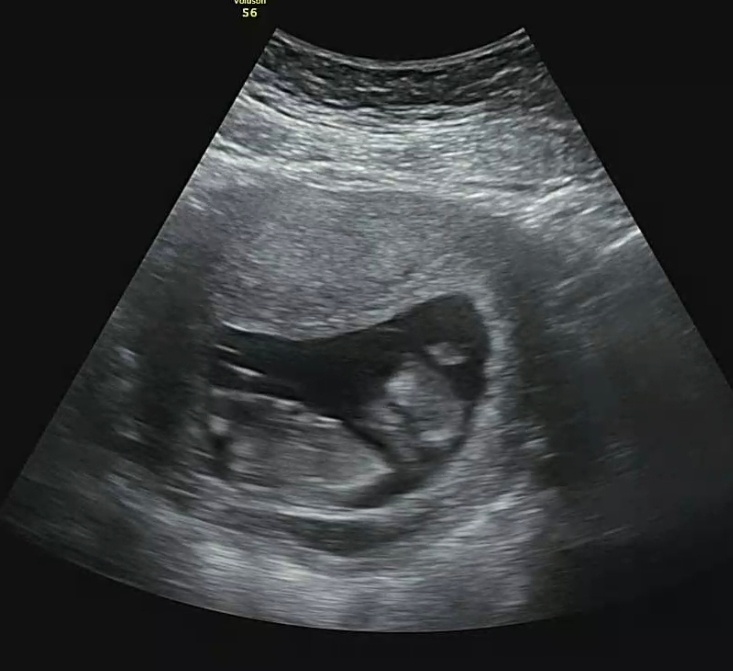

8주 6일 - 초음파 확인!

일주일마다 보고 있는 초음파!

일주일 만에 또 엄청 커져있는 뚝딱이!!

작아진 난황과 너무 귀여운 뚝딱이ㅠㅠ